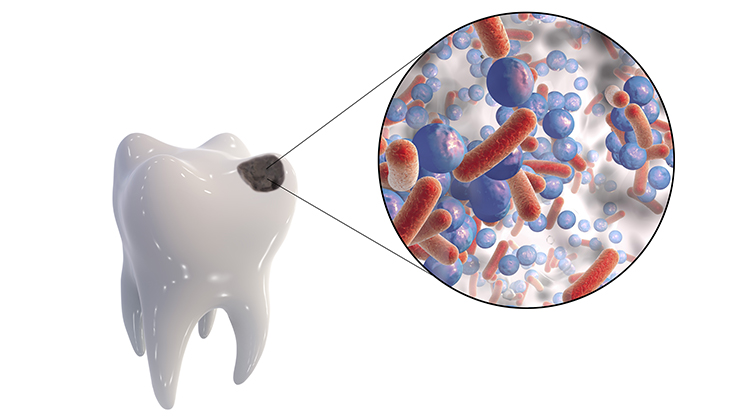

細菌(むし歯菌)

むし歯はお口の中のむし歯菌が酸をつくり、その酸によって歯が溶けてしまう病気です。私たちが毎日おこなう歯磨きは、お口の中からむし歯菌をできるだけ減らして酸の産出をおさえるためのもの。最低でも1日2回、とくに就寝前の歯磨きは徹底する習慣を身につけていきましょう